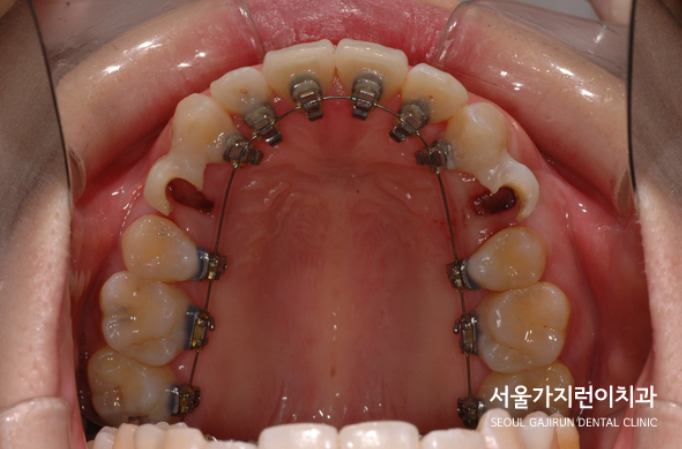

환자분의 경우 투명교정으로도 돌출입 교정이 가능했지만 상대적으로 치료기간이 길어질 것이 예상되어 설측교정을 선택하셨는데요. 서울가지런이치과 교정과 의원의 특화된 탄댐 아치 와이어 테크닉 방법을 이용해 상악 전치의 치근과 치관을 같은 비율로 후방이동시킬 수 있었습니다. 치료과정에서 돌출감 해소를 위해 상하악 제1소구치를 발치 했는데요. 발치간 공간을 폐쇄하기 위해 미니스크류도 식립하여 진행했습니다.

발치 공간이 메꿔지면서 입술이 들어가는 것을 확인할 수 있었는데요. 환자분의 경우 턱끝에 호두껍질 모양의 주름이 생기지 않길 희망하셨기 때문에 미니스크류를 식립한 후에 교정용 고무줄을 연결해 안정적으로 힘이 가해지도록 진행했습니다. 총 소요된 치아교정기간은 약 1년 6개월 정도인데요. 교정 치료 후 사진을 보면 옥니 느낌 없이 윗 입술이 들어간 것도 확인할 수 있었습니다.